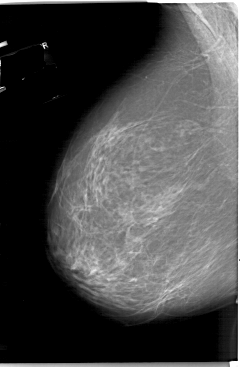

A_1330_1.RIGHT_MLO

LEFT_MLO LINES 6601 PIXELS_PER_LINE 4306 BITS_PER_PIXEL 12 RESOLUTION 43.5 NON_OVERLAY